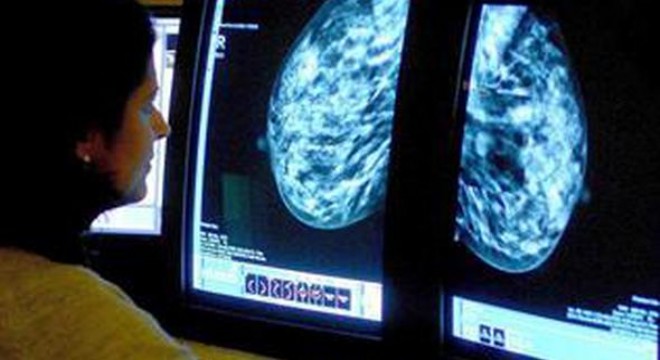

Avrupa’da yüzde üç olan meme kanseri görülme oranı Türkiye’de yüzde 17’ye yükseliyor. Aradaki fark, ölümlere neden olan meme kanserini ülke için önemli bir sorun haline getiriyor. Meme kanseri teşhisi konusunda açıklamalarda bulunan Türk Cerrahi Derneği Başkanı Prof. Dr. Çağatay Çifter şunları söyledi:

Kendi kendine muayene ile bulunan bir meme kanseri ‘erken meme kanseri’ değil. Biliyoruz ki erken tanı konulabilmesi halinde meme kanseri tedavi edilebilir bir hastalık. Risk altındaki grupların yıllık doktor ve görüntüleme kontrollerine gitmeleri gerekiyor. Yapılan birçok çalışmada, meme kanseri kendisi tarafından fark edilen hastaların, rutin taramalarla meme kanseri tanısı konulanlara göre yaşam sürelerinin ‘daha kısa olduğu’ görülüyor. Meme kanseri tanısının, hastanın kendi kendini muayenesinde fark edemeyeceği bir boyuttayken konulması hayat kurtarıcı. Meme kanserinden korunma yolu kendi kendine muayene değil, rutin doktor kontrolüdür.”